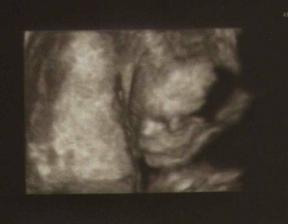

20.4.09 - velký UTZ na Genetice(10 hod) + kardio UTZ(14 hod) = 21tt+3

1.4.09 - poradna u gyn. - miminko má 258g, odpovídá 19tt+0(dle MS 18tt+5), je naprosto OK.